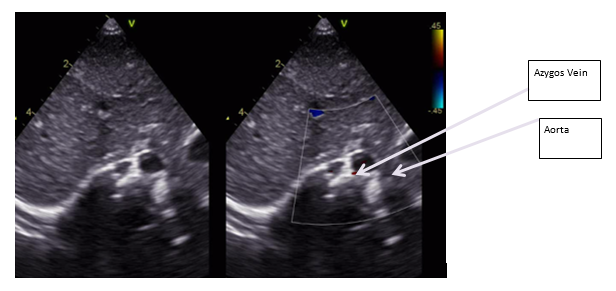

Postnatal ECHO revealed an Interrupted IVC (Figure 1) with venous return via the azygos vein (Figure 2 & Figure 3), draining into the superior vena cava (SVC), hepatic veins draining directly into the right atrium (RA), SVC draining into the RA and a small patent foramen ovale (PFO) with left-to-right shunting with normal cardiac anatomy with no abnormalities of the valves, aortic arch, outflow tracts, and no outflow tract obstruction.

Figure 2: Subcostal echocariographic situs view showing Azygos vein instead of IVC (IVC is usually seen on the right side and more superiorly).